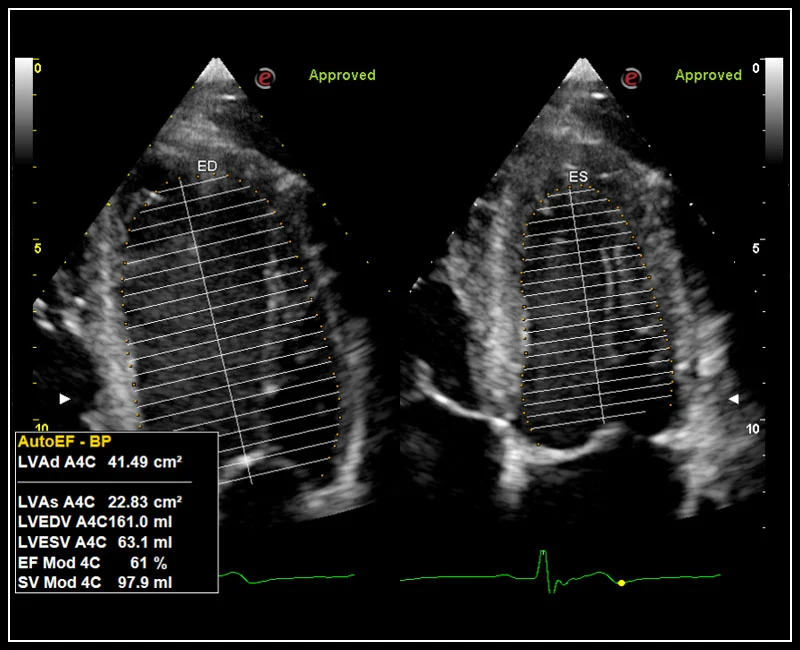

MyLab™X5 - AutoEF

MyLab™X5 - AutoEF

MyLab™X90 - AutoEF Automatic Ejection fraction assessment of the left ventricle

MyLab™X90 - AutoEF Automatic Ejection fraction assessment of the left ventricle

MyLab™A70 - AutoEF

MyLab™A70 - AutoEF